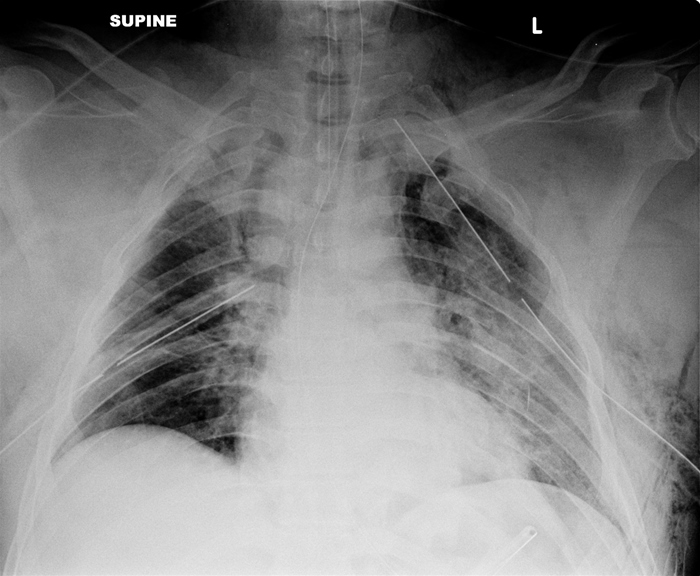

The first diagnostic study to evaluate a patient for a traumatic aortic rupture is a chest x-ray. Finding of a widened mediastinum on chest x-ray is highly concerning.

Pulmonary contusions are parenchymal injuries that can cause hypoxia in the acute setting. Classically, pulmonary contusions may not be immediately apparent radiographically, but later show a bilateral "white-out" appearance due to diffuse opacities.

Diaphragmatic ruptures most commonly occur on the left, because the liver prevents right-sided rupture. Two radiographic findings on chest x-ray are multiple air-fluid levels and presence of nasogastric tube in the thorax.

Elevation of the hemidiaphragm on the chest x-ray might be the only abnormal finding, but ultrasonography or CT scan of the chest is sometimes required if the chest x-ray does not visualize the area well. The small bowel is sometimes present in the thoracic cavity.